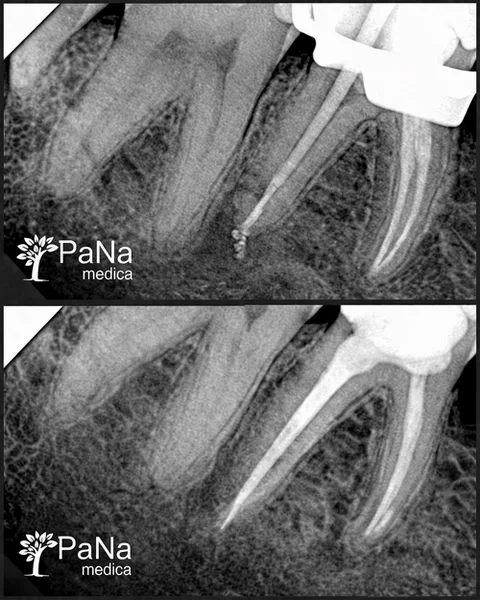

Stomatolog, endodonta / ponad 6 lat doświadczenia

„Zajmuję się leczeniem kanałowym i trudnymi przypadkami. To praca, w której nie ma miejsca na „mniej więcej” — liczy się precyzja i każdy detal.”